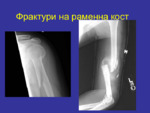

Фрактури на раменна кост

Презентации

по

Медицина

Фрактура – нарушаване целостта на дадена кост в различни оси. Видове фрактури...